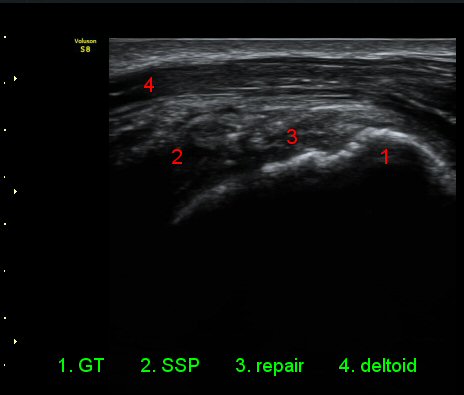

ÃÊÀ½ÆÄ °Ë»ç

ÀÌµÎ¹Ú±Ù°Ç È¾´Ü¸é°Ë»ç¿¡¼­ °ÇÁÖÀ§¿¡ ¼Ò·®ÀÇ ¼ö¾×Àú·ù¿Í Á¡¾×³¶³» ¾×Àú·ù°¡ °üÂûµÈ´Ù(»çÁø 1, 2).

¾î±ú¸¦ ³»Àü, ³»È¸Àü, ½ÅÀüÇÏ¿© ±Ø»ó°Ç°Ë»ç¿¡¼­ ±Ø»ó°Ç ÆÄ¿­ ÈÄ ¼ö¼úÇÑ ¼Ò°ß, ±Ø»ó°ÇÀÇ

Àú¿¡ÄÚ ºÎÁ¾°ú ºÎºÐÀû ÆÄ¿­, °í¿¡ÄÚ ºÀÇÕ»ç, ´ë°áÀýÀÇ ºÒ±ÔÄ¢º¯È­,À» º¸¿©ÁØ´Ù(»çÁø 6, 7, 8, 9)